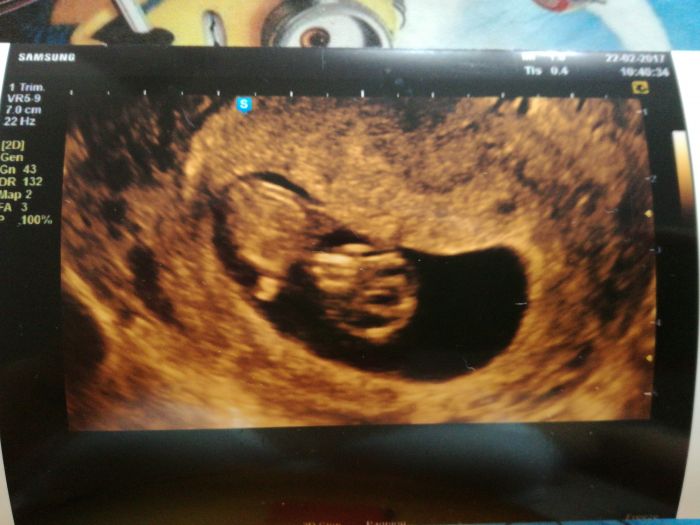

Ja jsem.dneska sla na kontrolu mimo termin 9+5 ,ze me taky boli bricho,ze ani nemuzu spat,ale miminko v poradku a dostala jsem prvni fotku :) jinak mamit klid a koupit si magnezium..na krev jdu 8.3.to zaplatim 560kc a 15.3.druha cast screeningu,to zaplatim 900kc,celkem silenost